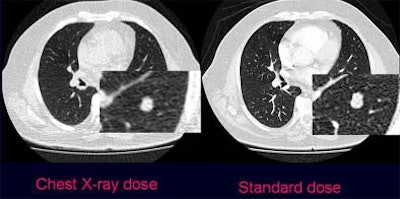

![]() |

| Axial images show pulmonary nodule in standard dose (right) and ultra-low-dose scan protocols in a 64-year-old patient with prostate cancer. The zoomed images show one of two metastases that were histologically confirmed and resected. All images courtesy of Dr. Valentina Romano. |

"There was moderate agreement in the readers' subjective confidence in pulmonary nodule detection between the two methods, (k = 0.437, p < 0.05)," Romano said, adding that the readers considered the low-dose method a hindrance for nodule characterization in 10.4% of nodules (k = 0.558, p < 0.04), with misses in the ultra-low-dose technique confined to the very smallest nodules. Edges were sometimes harder to define in the lowest-dose images, which could potentially raise questions about their morphology. Still, no nodule 2 mm or smaller was overcounted in the low-dose technique, while 16.1% were undercounted, she said.